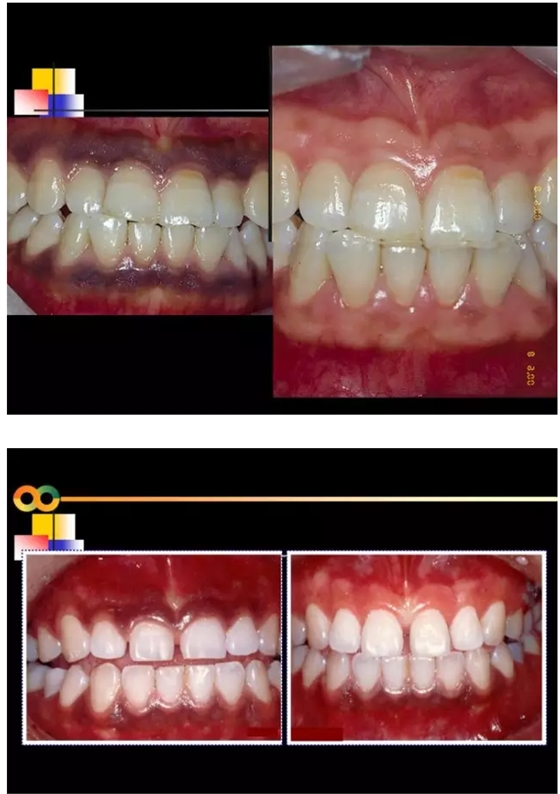

【牙科知識(shí)】牙周病相關(guān)手術(shù)圖解,非醫(yī)學(xué)專業(yè)勿點(diǎn)